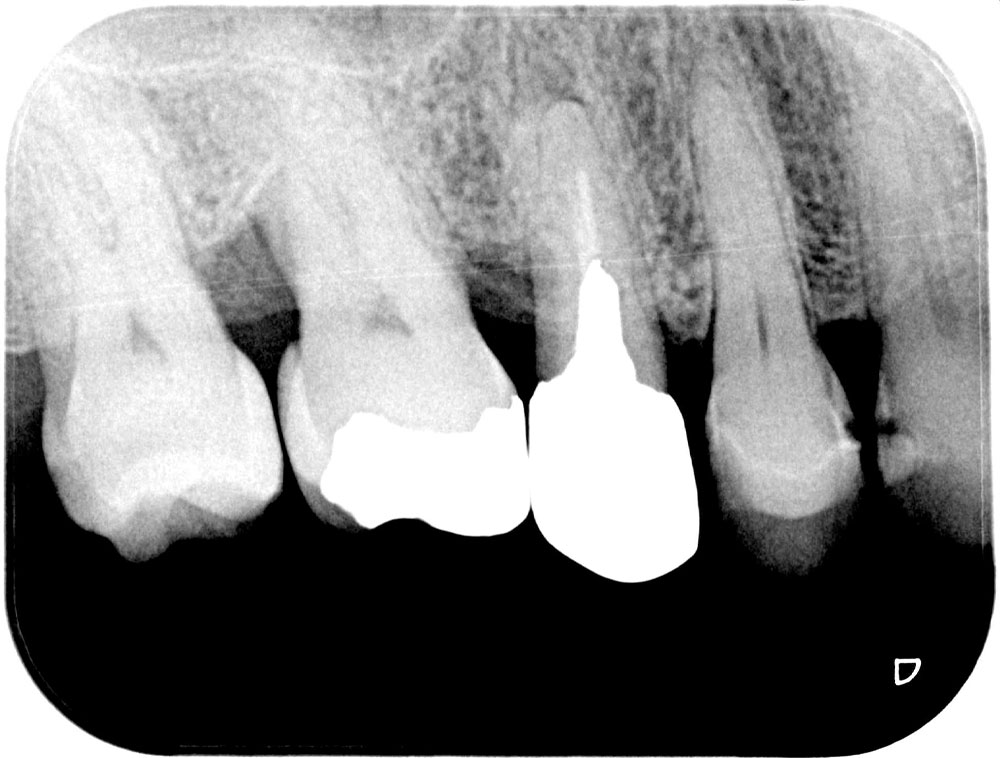

この患者さんもマウスピース矯正中に虫歯治療の必要があり、左上6番の虫歯治療することになりました。デジタルの歯科治療に豊富なノウハウを持つ恵比寿・広尾歯科はマウスピース再製作の費用や矯正期間遅延の心配することなく、矯正中も虫歯治療をおこなうことができます。

治療前レントゲン写真

治療後レントゲン写真

患者さんは30代の男性で、前歯が痛くてグラグラすると言うことで来院されました。 触診すると確かに、左上1番はグラグラと動いてこのままでは 歯が脱落する状況でした。 レントゲン、CTを撮影して骨の様子を確認したところ歯冠部と歯根で歯が折れ、残念ながら診断は破折でした。周囲の歯を保つためにもインプラントによる治療をご提案させていただき、患者さんの理解と同意を得ることができたので、骨造成も行いながら約1年で機能的・審美的に優れたインプラント治療を終えました。